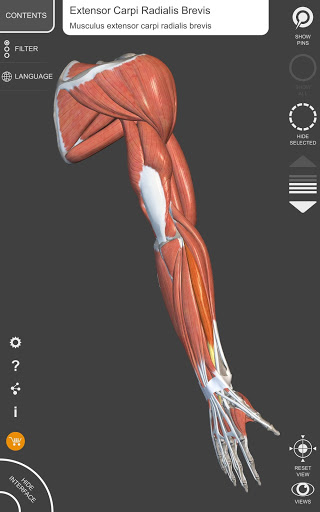

يتيح لك "Anatomy 3D Atlas" دراسة التشريح البشري بطريقة سهلة وتفاعلية.

من خلال واجهة بسيطة وبديهية، من الممكن ملاحظة كل بنية تشريحية من أي زاوية.

تتميز النماذج التشريحية ثلاثية الأبعاد بتفاصيل خاصة ودقة تصل إلى 4K.

يسهل التقسيم حسب المناطق والمناظر المحددة مسبقًا مراقبة ودراسة الأجزاء الفردية أو مجموعات الأنظمة والعلاقات بين الأعضاء المختلفة.

• الجهاز العضلي الهيكلي

• تصور العضلات من خلال مستويات الطبقات من الطبقات السطحية إلى الأعمق

• من خلال تحديد نموذج أو دبوس، يظهر المصطلح التشريحي ذي الصلة

• وصف العضلات: الأصل والإدخال والتعصيب والعمل